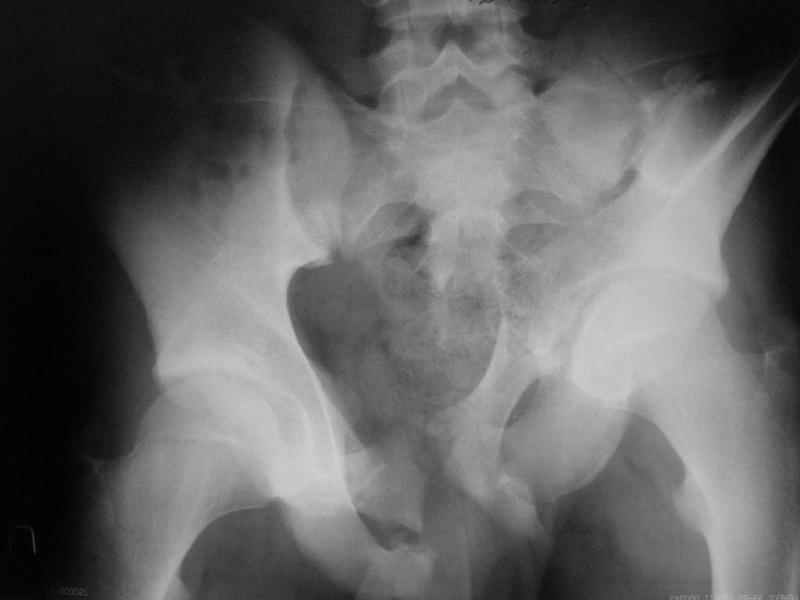

Ув. коллеги, к нам поступил молодой человек 17 лет. Травма в июле 2005- ДТП, т.е. 3 мес назад. Лечился консервативно в "гамаке" 1,5 мес., затем ходьба с костылями без опоры на левую нижнюю конечность, начал на нее опираться 1 нед назад.

В настоящее время имеется укорочение порядка 4-5 см, выраженная хромота, передвигается с одним костылем. Кроме того беспокоят боли в пояснично-крестцовой области при ходьбе, неудобство при сидении, невозможность лежать на спине "на жестком", а также на левом боку (субъект худощавый, боль в области крыла) хромота, длительное пребывание на ногах невозможно.

Учитывя наличие участков сращений, помогите опредилиться с тактикой.

Наш план пока такой: 1. выполнить остеотомии в участках сращений 2.постепенно аппаратом низвести смещенную половину таза. 3.выполнить внутренний остеосинтез передних и задних отделов.